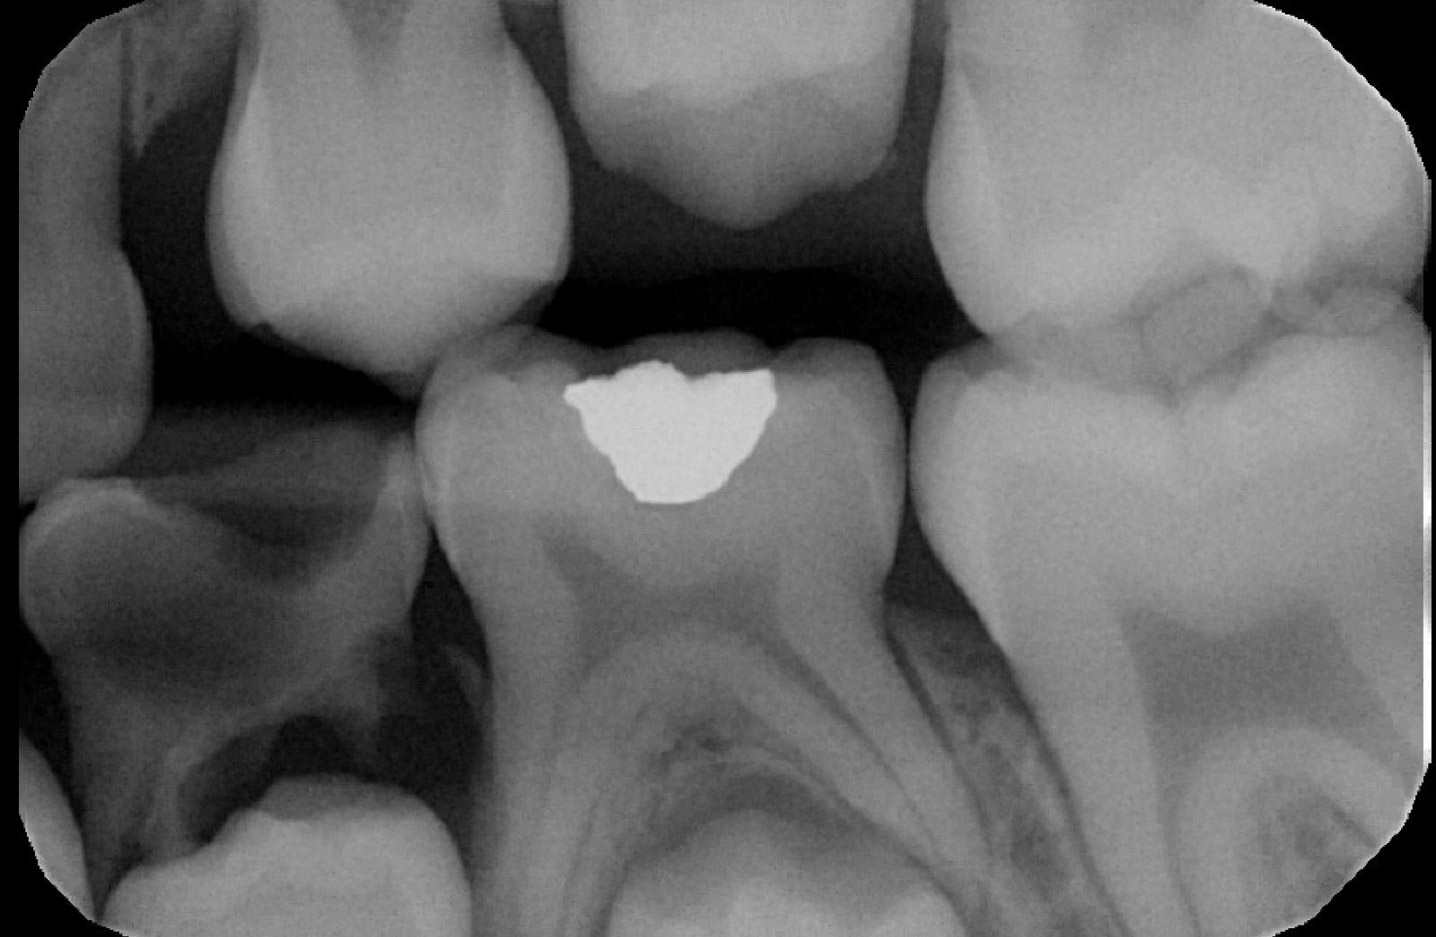

Patient presented to NYUCD to visit the dentist for the first time in 2017. These BWs and PAN were taken then.

Figures 9 & 10: Preoperative bitewings of Right and Left

Figure 11: Preoperative Panoramic image

Unfortunately, due to the amount of dental treatment needed and number of dental visit needed, patient and mother never returned back to NYU dental clinic.

Due to the clinical carious lesions present - 2 BW radiographs were recommended to observe any interproximal carious lesions (also to update the treatment plan that was never fulfilled) and PA#8 to observe the location of mesiodens and any update in eruption of #8 or the mesiodens.

Radiographic Interpretation revealed: Carious lesions in #3-O, #A-O, #14-O, #19-OB, #K-MOD, root tip present in tooth #L, #30-O, Mesiodens present ( disrupting the proper eruption of tooth #8) ***